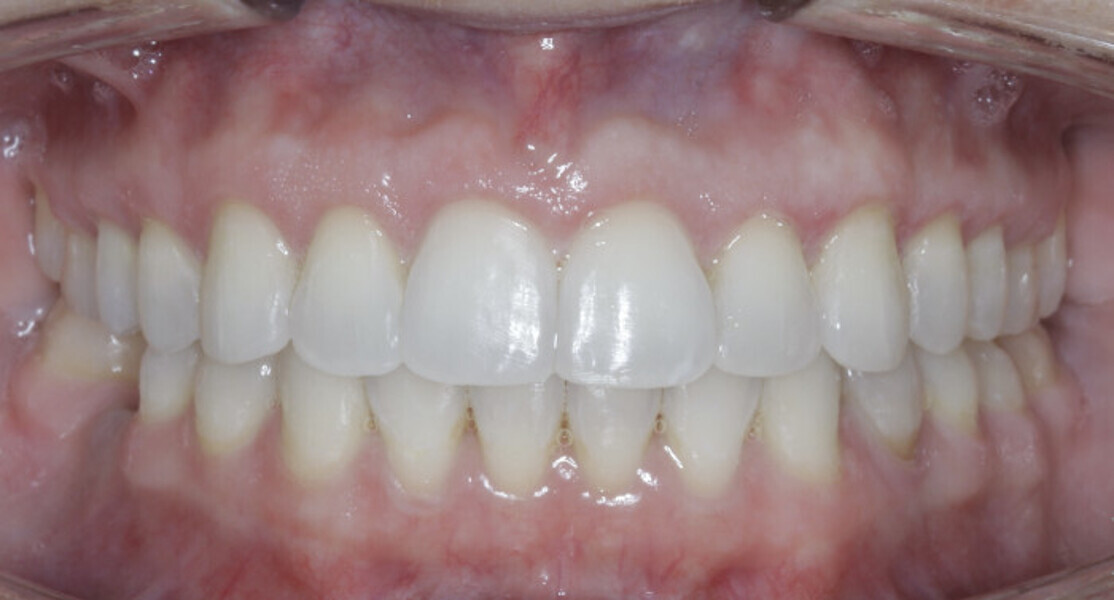

New Age orthodontics and orthopaedics with temporary anchorage devices